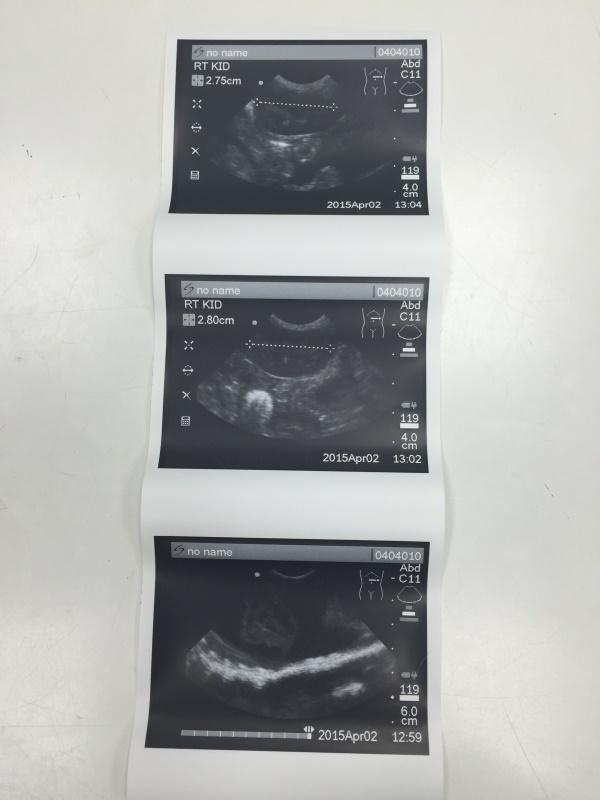

到院時小美短的體態背脊突出,腹部腫大,眼睛有分泌物,後腿無力,站立時會東倒西歪,抽血檢驗A/G比偏低,超音波掃描有腹水,醫師研判是腹膜炎的機率極大,開始給予類固醇、食慾促進劑和灌食,希望貓咪在治療下最後的日子可以開開心心的,每個人摸摸抱抱小美短都會呼嚕嚕,眼睛眨啊眨,靜靜的把頭靠在手掌中,多麼令人不捨的孩子...很遺憾在住院第四天,小美短完成她一生功課畢業了...繁殖只會造就更多的悲劇,生了病的孩子,沒有販售利用的價值就隨意丟棄,每個生命都該被好好呵護,就算是最後也該讓她在溫暖中離開,感受生命的溫暖,而不是生命的殘酷。